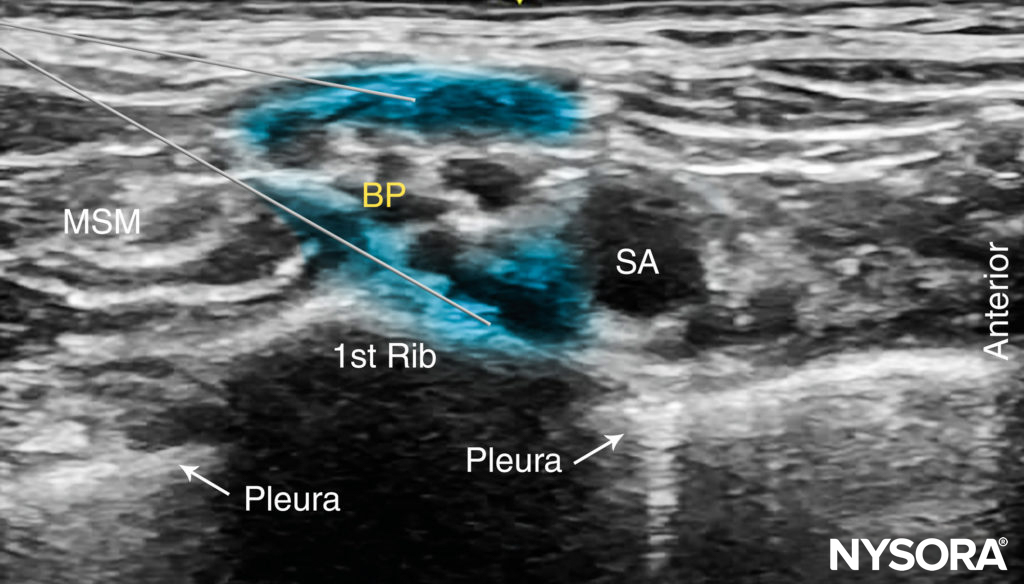

With the patient in the proper position, the skin is disinfected and the transducer is positioned in the transverse plane immediately proximal to the clavicle, slightly posterior to at its midpoint. The transducer is tilted caudally, as if to image the chest contents, to obtain a cross-sectional view of the subclavian artery (Figure 5). The brachial plexus is seen as a collection of hypoechoic oval structures posterior and superficial to the artery. Color Doppler should be routinely used prior to needle insertion to rule out the passage of large vessels (ie, dorsal scapular artery, transverse cervical artery, suprascapular artery) in the anticipated trajectory of the needle.

Nerve stimulation (0.5 mA, 0.1 msec), is often associated with a motor response of the arm, forearm, or hand. Note, however, that motor response may be absent despite accurate needle placement. Insertion of the needle into the sheath is often associated with a palpable “pop.” After careful aspiration, 1–2 mL of local anesthetic is injected to confirm proper needle placement. When the injection displaces the brachial plexus away from the needle, an additional advancement of the needle 1–2 mm closer to the plexus may be required to accomplish adequate local anesthetic spread (Figures 7, 8, and 9). When the injection of local anesthetic does not appear to result in a spread around the brachial plexus, needle repositioning may be necessary. Typically, 20–25 mL of local anesthetic is required for adequate nerve block. It has been suggested that lower volumes can be used in older patients. (see Figure 7). Supplementary video related to this nerve block can be found at Ultrasound-Guided Supraclavicular Brachial Plexus Nerve Block Video.

FIGURE 7. The desired spread of local anesthetic (blue-shaded areas) in two different needle positions to accomplish brachial plexus (BP) nerve block. Local anesthetic should spread within the connective tissue sheath resulting in separation of the brachial plexus trunks posterior to the subclavian artery (SCA).

FIGURE 8. Ultrasound image simulating needle path and expected local anesthetic spread after a single injection within the connective tissue sheath surrounding the brachial plexus. Additional monitoring (eg, nerve stimulation and injection pressure) is recommended to decrease the risk of intrafascicular injection.

FIGURE 9. Ultrasound-guided supraclavicular brachial plexus nerve block simulating a single injection between the subclavian artery (SA) and the first rib.